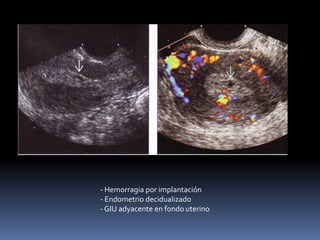

- Hemorragia por implantación

- Endometrio decidualizado

- GIU adyacente en fondo uterino

 Hemorragia perigestacional. - Hemorragia peri gestacional amplia

- Hemorragia porimplantación - Endometrio decidualizado - GIU adyacente en fondo uterino